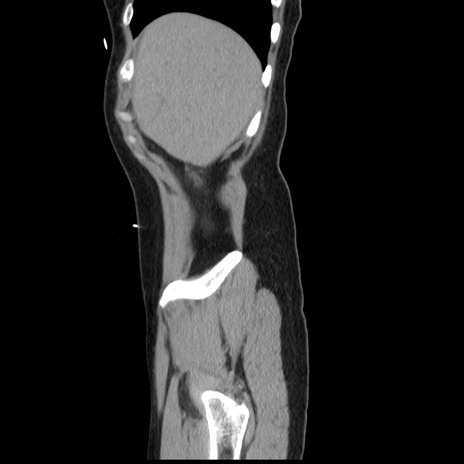

症例10(矢状断像)

【症例】 50歳代女性

【主訴】 腹痛

【現病歴】前日生レバーを食べた。今朝に排便あり。 昼前に突然発症の腹痛を生じ、当院救急外来を受診した。

【既往歴】 子宮筋腫にてで子宮全摘後

【身体所見】 意識清明、腹部:平坦、軟、下腹部やや左を中心に圧痛・反跳痛あり、筋性防御あり

【データ】WBC 7800、CRP 0.07